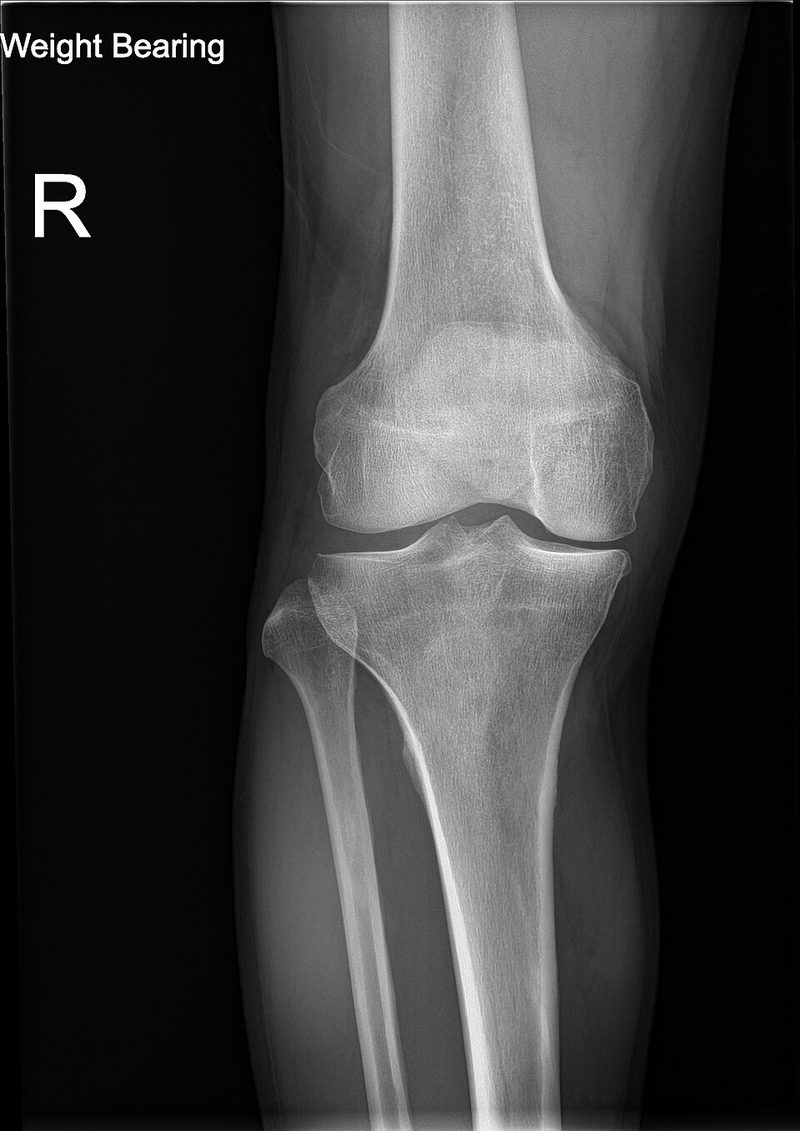

Radiografia de osteoartritis en rodilla izquierda

Wikimedia Commons / CC BY-SA 4.0

RadiografiaDesgaste del cartilago, espolones oseosOsteoartritis